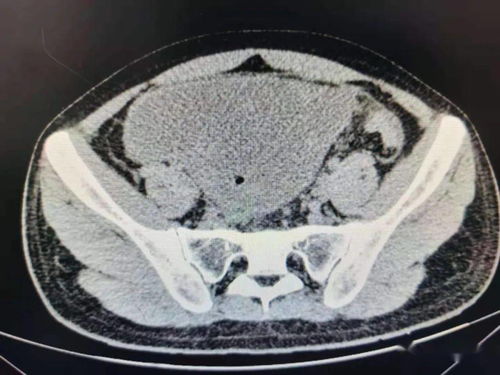

血液检查是检测肿瘤标志物的重要手段,但需注意,这些指标的升高并不一定意味着肿瘤的存在。影像学检查如B超、低剂量螺旋CT和PET-CT也是初步筛查的重要工具。

不同部位的肿瘤需要采用不同的检查手段。例如,肺癌推荐低剂量螺旋CT,消化道肿瘤则推荐胃肠镜检查。肝癌可考虑B超结合甲胎蛋白(AFP)检测,而乳腺癌和宫颈癌也有特定的检查手段。